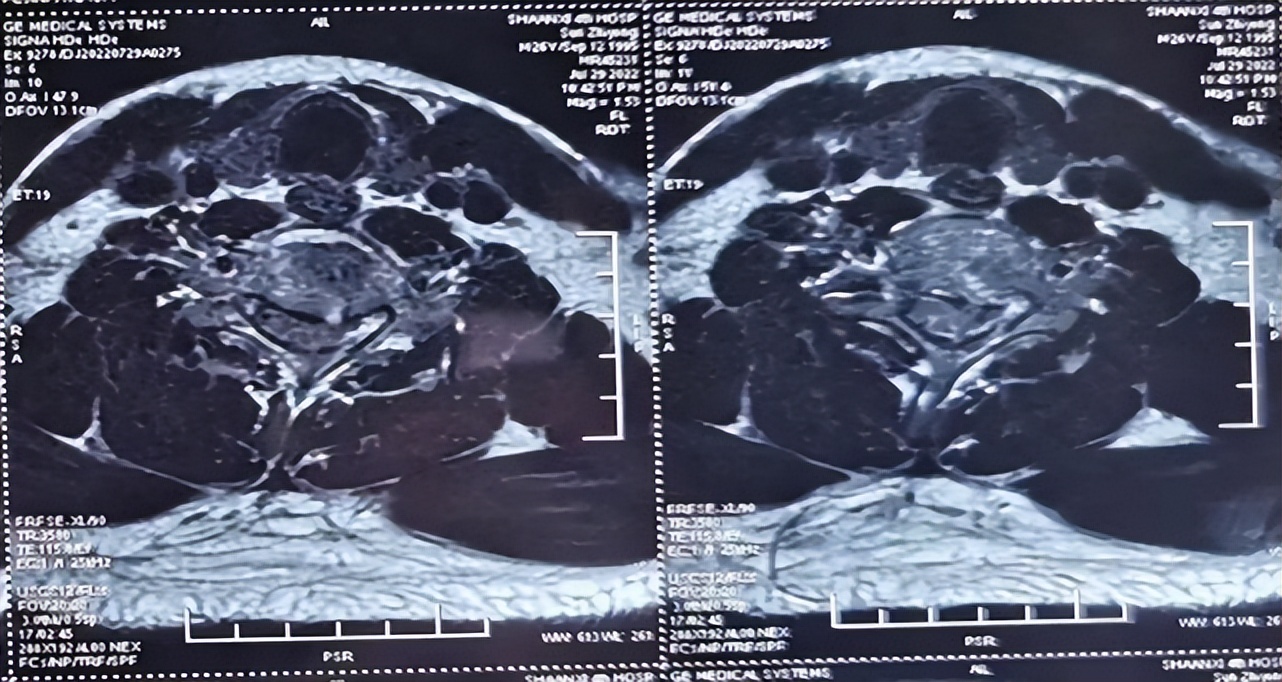

术后脊髓损伤平面

术后,结合ERAS现状及脊髓损伤救治标准,急诊EICU唐海峰主治医师及其团队精细化的围术期管理:24小时的标准的大剂量激素冲击+雾化排痰+床上的肺功能锻炼+被动及主动下肢,积极的抗炎和早期肠内营养的供给。未出现呼吸衰竭、下肢静脉血栓及压疮等并发症,术后4天转入康复科进行康复治疗。在多方面的努力下,大小便功能逐步恢复,伤后4周复查,患者可下地行走,双上肢肌力3级,双下肢肌力达到4级+,痛温觉、触觉逐渐恢复。 伤后5周随访,患者双上肢前臂尺侧和尺侧三指麻木、疼痛,双下肢麻木。双上肢肌力三级+,双下肢肌力5级-,行走已经完全不是问题,且大小便恢复正常,治疗效果良好。